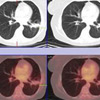

At the end of cryoablation, the resulting ice ball encompasses the tumor as well as a 1 cm surrounding margin.

Follow-up CT demonstrates no residual viable tumor.